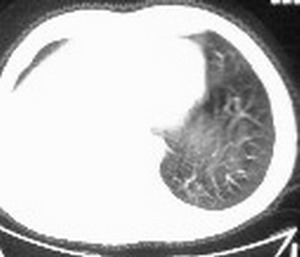

右肺下叶支气管闭塞,伴下叶实变不张。建议增强及纤支镜。

右肺下野后部均匀低密度影,边缘锐利,前缘外突(不支持肺不张),纵隔内未见明显肿大淋巴结,右下肺门结构显示欠清,临床资料太过简单,考虑右侧后胸部包裹性积液。其他待排。建议密切结合临床其他检查。